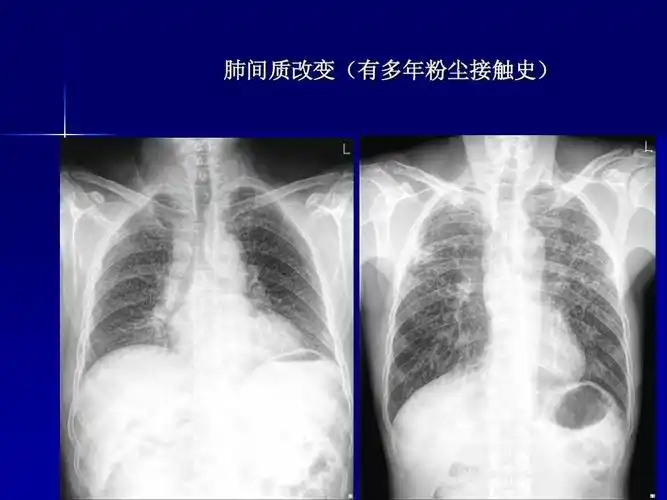

肺部疾病影像学阅片 一,正常胸片 正常胸片(正位片)

x线胸片阅读基础ppt